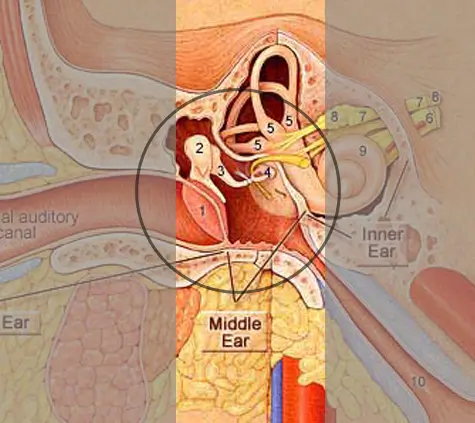

- The eardrum vibrates in response to sound waves

- Tiny bones amplify vibrations to the inner ear

Conductive hearing loss happens when sound is unable to pass through the outer ear, ear canal, or middle ear to reach the inner ear. It may be caused by infections, fluid buildup, a perforated eardrum, or structural issues. This condition reduces sound volume, making soft or distant sounds harder to hear — but clarity remains unaffected

Structural issues may be addressed through surgical intervention like tympanoplasty or ossicular reconstruction